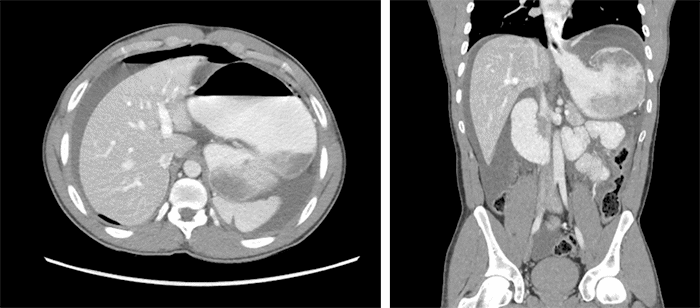

A chest X-ray revealed a mass-like opacity in the left mid abdomen, extending to the right paraspinal region and causing displacement of bowel loops inferiorly and to the right side (Figure 1). This prompted further evaluation with a computerized tomography (CT) scan, which indicated findings suggestive of gastric volvulus (likely mesentero-axial) with perforation, along with a large amount of pneumoperitoneum and free fluid (Figure 2).

Figure 2. Pneumoperitoneum and Free Fluid with Suspected Mesentro-axial Gastric Volvulus. Published with Permission